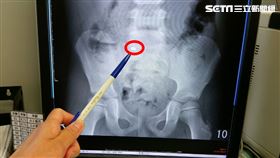

女童發燒、畏寒 竟是泌尿道感染

台中一名國小女童因連續兩天發燒、畏寒、解尿疼痛至長安...

5歲女童誤吞磁鐵 醫:已跑到小腸…

5歲王姓女童日前玩耍時,不小心吞進一顆0.5公分磁鐵...